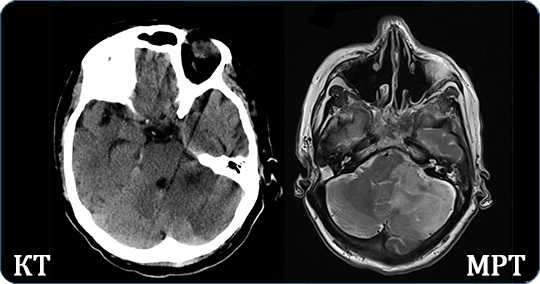

Для диагностики пороков сравнивают результаты КТ и МРТ

Исключить гипоксические и травматологические проявления позволяют инструментальные способы диагностики - УЗИ, нейросонография, МРТ и КТ. Процедур достаточно для выявления аномалий развития, кист, гетеротопических участков.